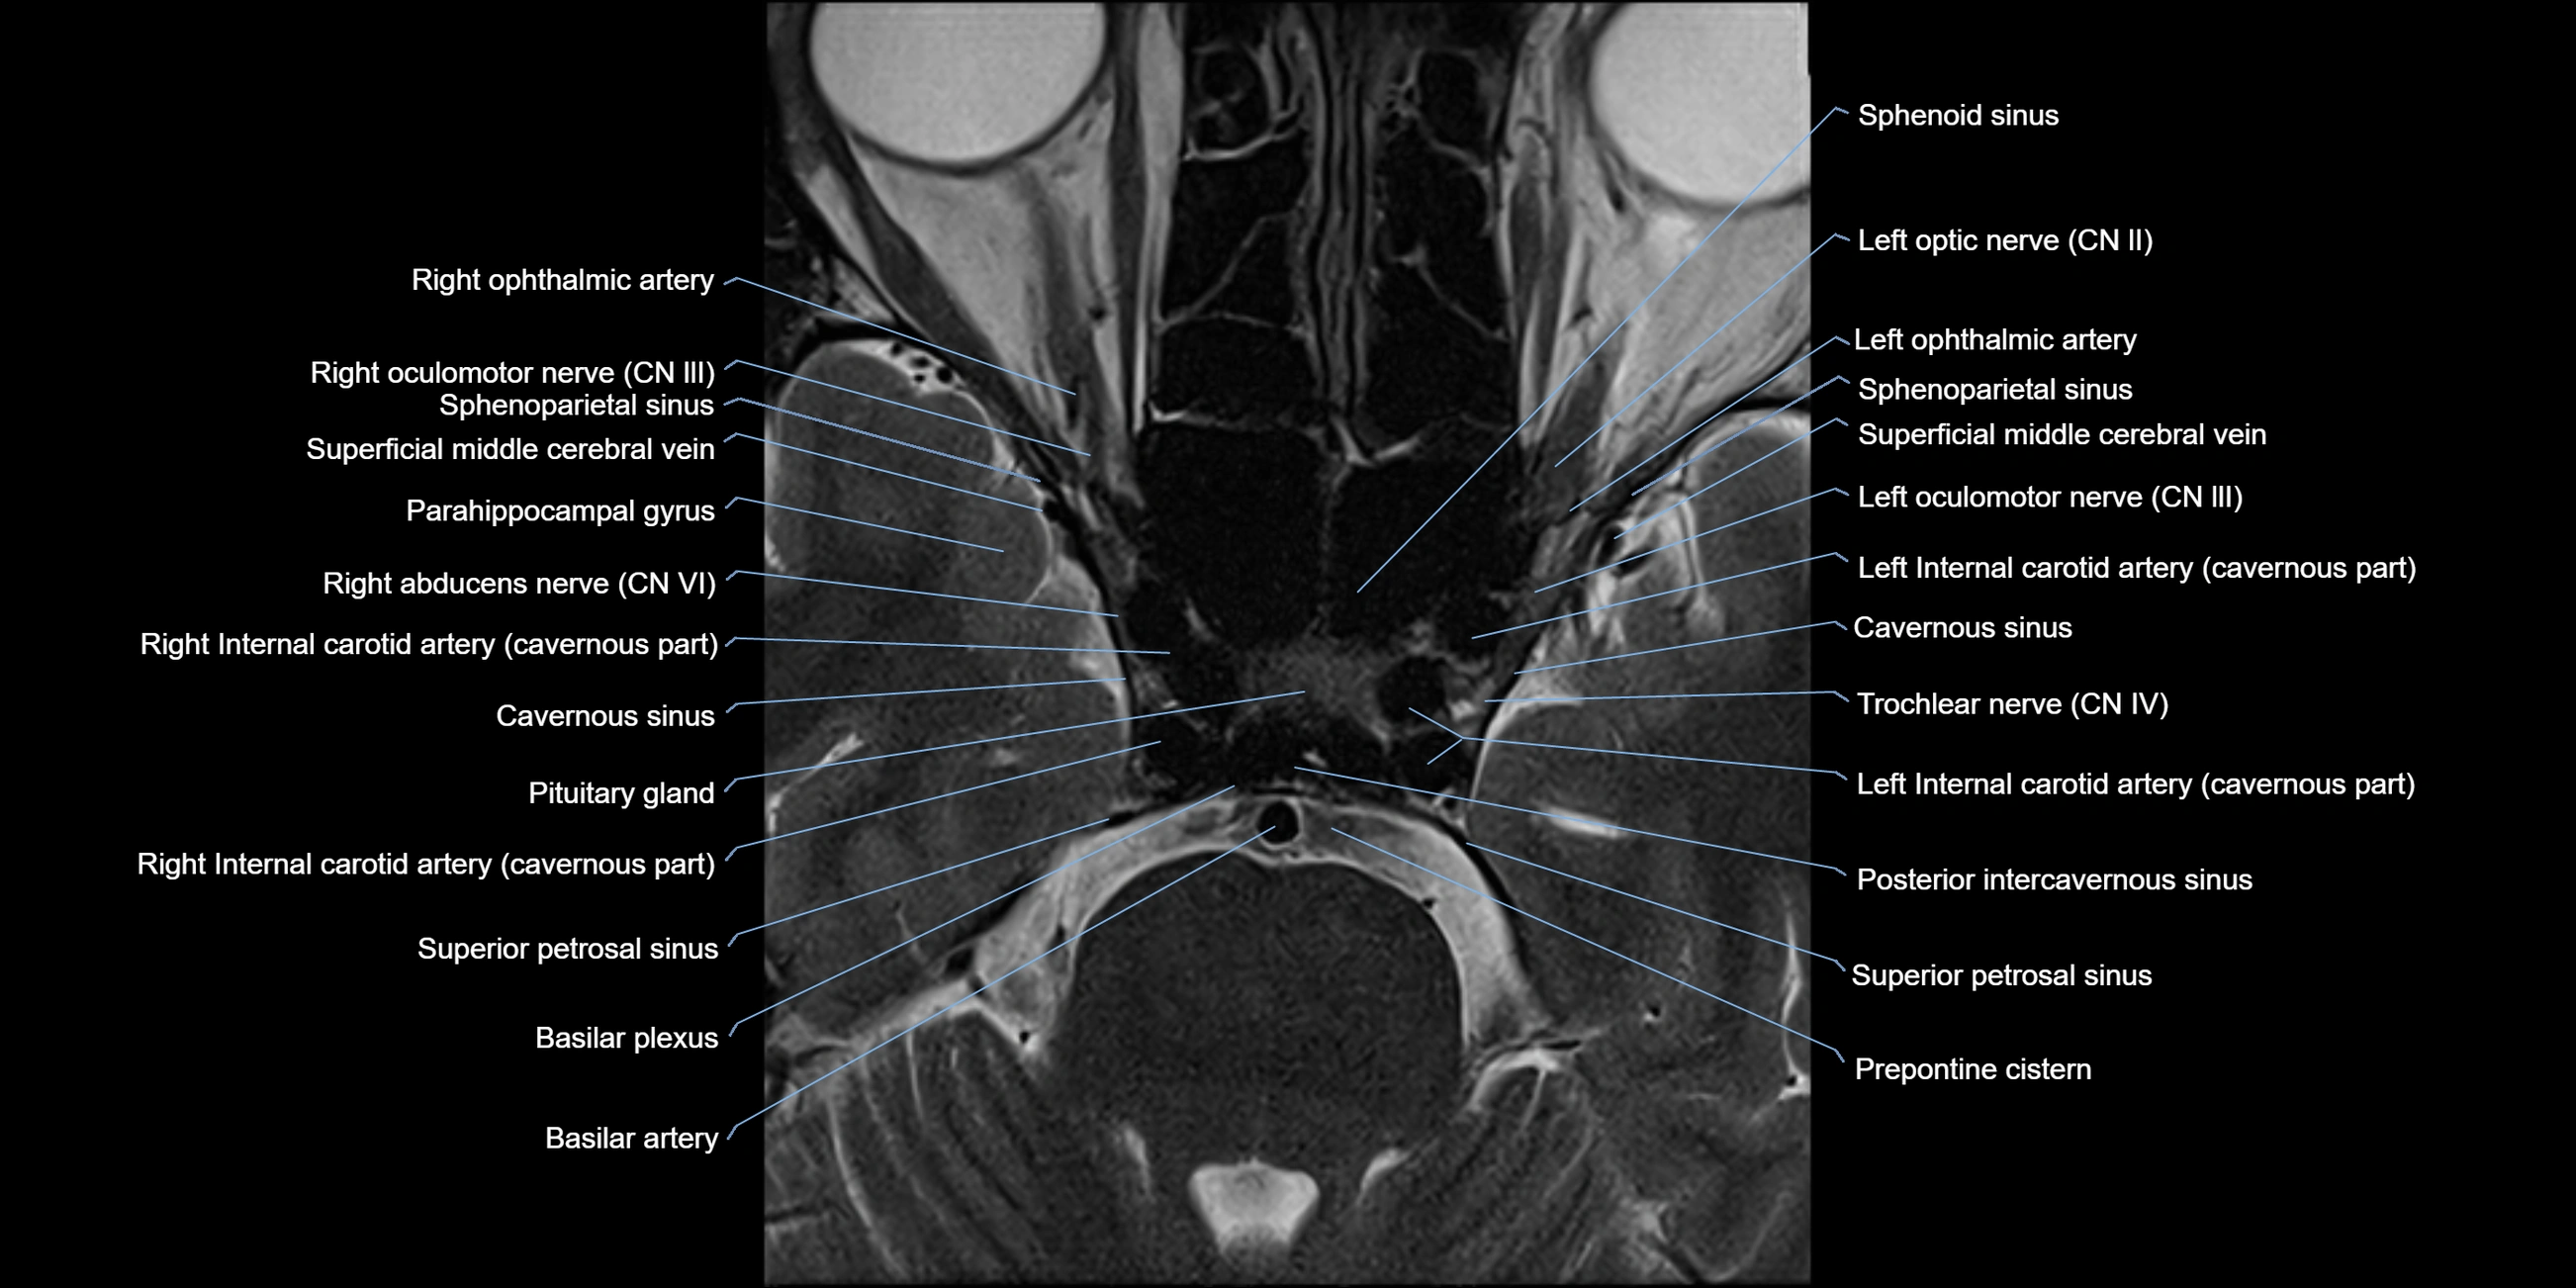

MRI Appearance

-

The abducens nerve is a small, thin, linear structure

Best visualized on high-resolution T2-weighted 3D MRI sequences (e.g., FIESTA or CISS)

Seen as a hypointense (dark) line running from the brainstem at the pontomedullary junction, traversing the prepontine cistern, and entering Dorello’s canal under the petrosphenoidal ligament, then into the cavernous sinus, and finally the orbit

May be challenging to visualize in standard MRI due to its small size

Pathology may be inferred by absence, displacement, or enhancement of the nerve

MRI images